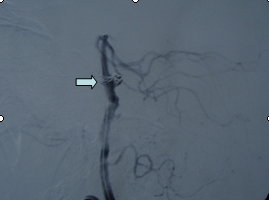

吴某,56岁,因突发昏迷1小时急诊入院。入院时深昏迷,呼吸微弱,血氧和血压降低,双侧瞳孔散大,对光反射迟钝,急诊头颅CT提示蛛网膜下腔出血。入院诊断考虑是脑动脉瘤破裂,紧急行气管插管、止血降颅压等抢救措施,同时放射科陆秀伟主任急诊行全脑血管造影,结果提示基底动脉巨大的动脉瘤(图一)。科主任范学政教授紧急组织全院会诊,组成了包括神经外科、重症医学科、呼吸科、放射科专家抢救小组,采取镇静、脱水、抗血管痉挛以及支持和对症等抢救措施,并病情和影像资料传输到神经外科协助医院四川大学华西医院神经外科远程会诊,会诊认为该病人最佳的治疗方案是行血管内介入治疗。经过充分准备,于入院4日后在华西医院神经外科张昌伟教授联合瑞康医院神经外科医生为患者进行了支架辅助下基底动脉瘤弹簧圈栓塞术,术后行脑血管造影显示动脉瘤完全栓塞(图二)。术后继续予抗血管痉挛等治疗,术后第二天出现呼吸衰竭,肺部感染,后经转入ICU、呼吸科、予以支持、抗感染治疗等综合治疗,术后10天病人清醒,目前患者已经康复出院。

动脉瘤介入栓塞后